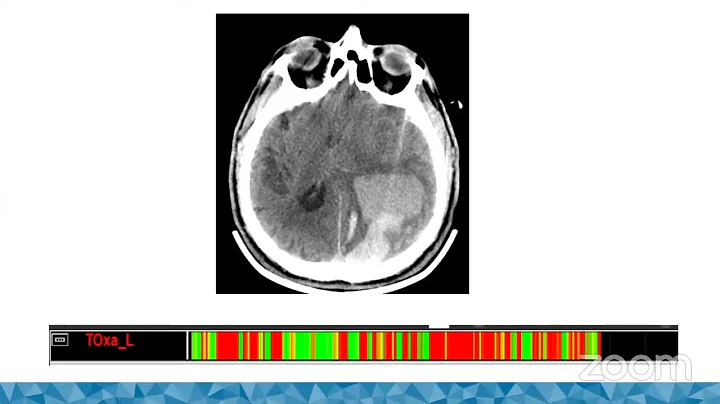

Invasive Multimodality Brain Monitoring

Scientific presentation on Brain Gliomas by Dr Ulrick Sidney. Neurosurgical.TV performs frequent webinars concerning ...